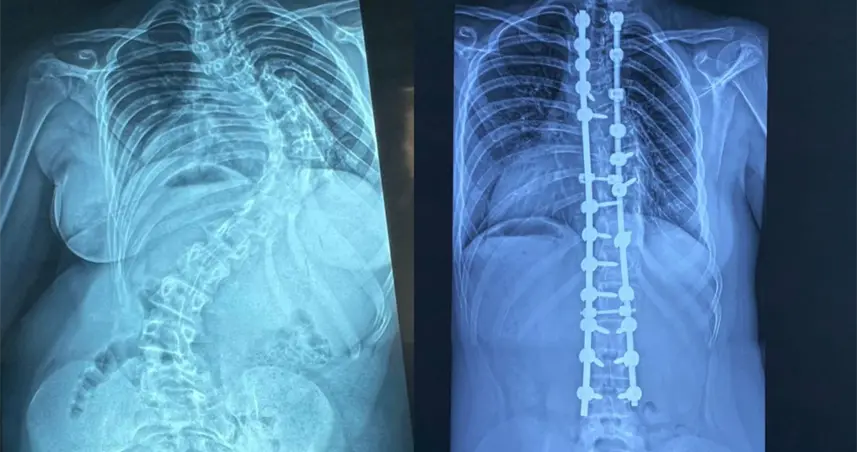

Realizan cirugías deformidades columna pediátrica para mejorar calidad de vida.

La escoliosis es una desviación de la columna vertebral mayor de 15 grados. El especialista detalló que la forma más frecuente es la idiopática del adolescente.

Advirtió que, cuando progresa, puede comprometer órganos vitales.

"Es una patología que básicamente va a mermar la calidad de vida de los pacientes, porque esas desviaciones que continúan progresando durante el crecimiento pueden comprimir órganos internos como el corazón y los pulmones", explicó.

Sobre los resultados, destacó que muchos pacientes intervenidos hoy llevan una vida normal.

"Después de una cirugía como esta pueden hacer su vida prácticamente normal, en igualdad de condiciones que cualquier otro niño".